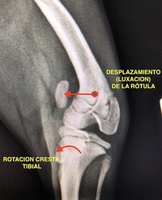

La rótula ( un hueso incluido dentro del tendón más grande de la extremidad posterior, el tendón del cuádriceps) está en condiciones normales “encajado” entre dos paredes verticales de hueso ( las crestas trocleares del fémur), que permiten el movimiento de arriba abajo ( el que se produce cuando el animal flexiona y extiende la rodilla), pero no el movimiento de la rótula saltando esas crestas trocleares. Cuando de forma congénita (desde el nacimiento) o traumática esa rótula salta la cresta medial (interna) o lateral (externa), se produce una luxación de rótula medial o lateral respectivamente.

La LR Grado IV, por el contrario, es aquella en la que la rótula está permanentemente luxada y es casi imposible devolverla manualmente a su sitio original. Las deformidades de cadera, fémur y tibia son severas y la cojera suele ser de no apoyo y contínua (foto).

Se debe confirmar el diagnóstico de LR con una manipulación básica, y luego cuantificar las deformidades que acompañan la LR en el resto de los huesos de la extremidad con una radiografía.

- TRANPOSICIÓN DE CRESTA TIBIAL. Es una osteotomía ( corte) de una parte pequeña de la cresta tibial de la tibia donde se inserta el tendón del cuádriceps que lleva incluida la rótula. Una vez cortado, se le reposiciona con unas pequeñas agujas metálicas en una localización más adecuada para neutralizar la luxación